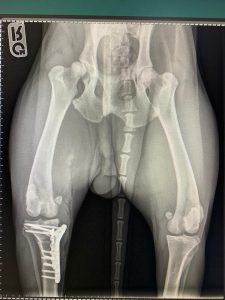

Hirurško liječenje rupture prednjeg križnog ligamenta koljena - TPLO

Za razliku od tradicionalnih metoda koje pokušavaju zamijeniti ili rekonstruisati ligament, TPLO mijenja biomehaniku koljena. Tokom zahvata, hirurg reže tibijalnu ploču (gornji dio goljenične kosti) i rotira je pod precizno izračunatim uglom kako bi se smanjio nagib zgloba. Time se eliminira klizanje femura po tibijalnoj ploči, koje nastaje zbog puknuća ligamenta, i stabilizira koljeno bez potrebe za ligamentom.

Nakon zahvata, preporučuje se strogo kontrolisana fizička aktivnost i rehabilitacija kako bi se osigurao optimalan oporavak. Veterinarski tim prati napredak psa kroz redovne kontrole i eventualne dodatne terapije.